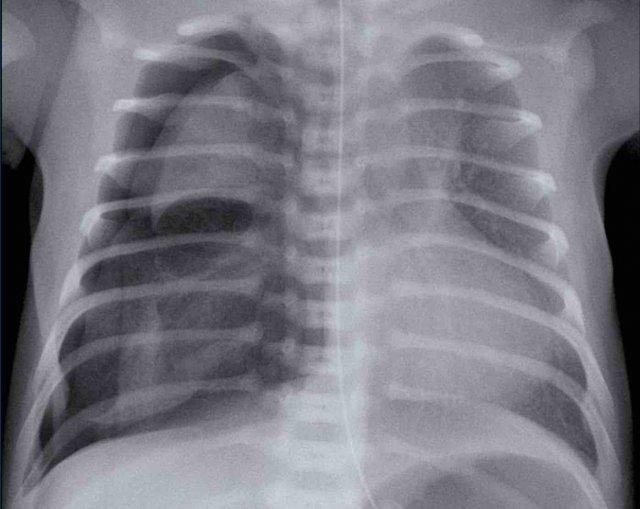

Hình ảnh của một trẻ sơ sinh có suy hô hấp.

Tuổi thai 37 tuần

Sau mổ lấy thai lần đầu.

Hình bên trái

Ứ khí quá mức ở bên trái.

Di lệch nhẹ các cấu trúc đường giữa sang phải.

Có thể thấy tràn khí màng phổi ở bên trái (mũi tên)

Hình ảnh bên phải

Trên phim X-quang ngực chụp theo dõi, tràn khí màng phổi đã tự khỏi.

Tràn khí màng phổi có thể rất khó nhận biết, vì trong nhiều rối loạn phổi ở trẻ sơ sinh, phổi không đàn hồi và sẽ không xẹp lại.